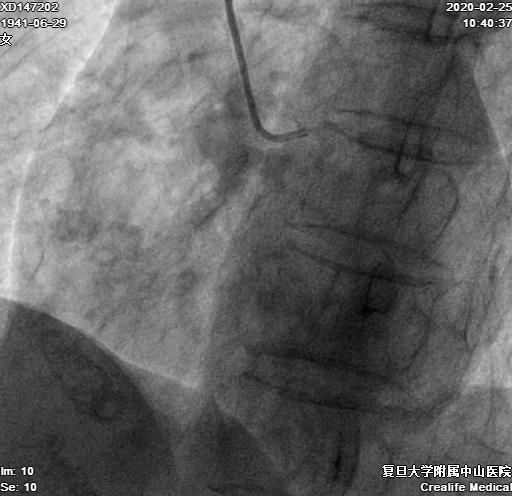

LM未见狭窄、LAD近段狭窄50%,中段30%,D1近中段狭窄80%,、LCX中段狭窄30%、OM未见明显狭窄,RCA近段狭窄50%,中段完全闭塞,远段由自身桥侧枝及心外膜侧枝血管提供显影(图1-3)

图1-3